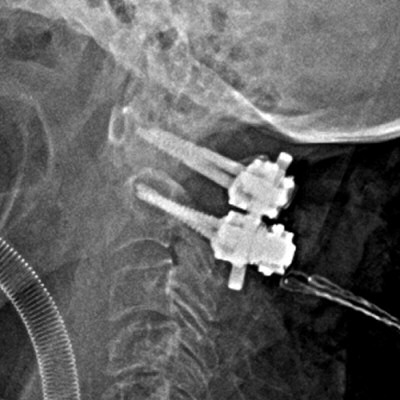

Exempel på dens-fraktur typ 2 före och efter fixation.